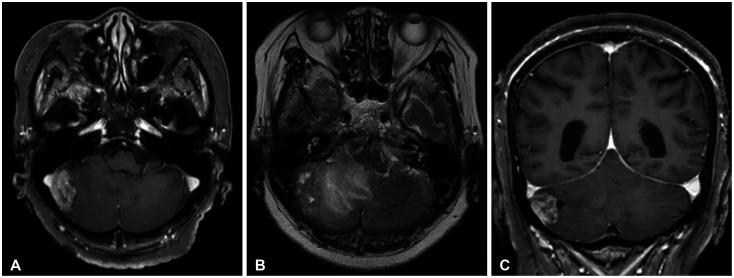

We report complete remission of dural-based leptomeningeal metastasis (LM) in an 80-year-old female patient with non-small cell lung cancer (NSCLC) by osimertinib. She was diagnosed with NSCLC (adenocarcinoma, T4N3M1a) 8 years ago. Mutation analysis of biopsied tissue revealed exon 19 deletion positive, and gefitinib was prescribed. Follow-up chest CT showed a radiological response, and whole-body positron emission tomography 3 years later revealed the disappearance of the previous high-uptake lesions. The medication was continued for maintenance but stopped 4 years later due to intolerable dermatitis. Two years after discontinuing chemotherapy, the patient had a gait disturbance, and brain MRI revealed a right cerebellar mass (diameter [d]=3 cm) with peritumoral edema, compatible with solitary brain metastasis. Retromastoid suboccipital craniotomy and gross total removal of the dura-attached lesion were performed. As the systemic cancer status evaluation revealed no radiological cancer lesion, only tumor bed radiation therapy was given (4,000 cGy/10 fractions) without re-introducing gefitinib. She was followed with a brain MRI at 6-month intervals, and a brain MRI 2 years postoperatively revealed a dural-based extra-axial mass in the left prepontine cistern (d=2.2 cm). Serial cerebrospinal fluid (CSF) cytology was positive for cancer cells. Upon LM diagnosis, the third-generation receptor tyrosine kinase inhibitor osimertinib was given. Two-month follow-up CSF cytology and five consecutive tests over 14 months demonstrated negative conversion. Five-month follow-up brain MRI revealed near complete remission of dural-based LM, and the response was maintained until the 13-month follow-up brain MRI.

我们报告了一位80岁的女性非小细胞肺癌(NSCLC)患者通过奥希替尼治疗硬脑膜脑膜转移(LM)完全缓解的病例。她在 8 年前被诊断为非小细胞肺癌(腺癌,T4N3M1a)。活检组织的突变分析显示 19 号外显子缺失为阳性,医生给她开了吉非替尼。随访的胸部 CT 显示有放射反应,3 年后的全身正电子发射断层扫描显示之前的高吸收病灶消失了。患者继续接受药物维持治疗,但 4 年后因无法忍受皮炎而停药。停止化疗两年后,患者出现步态障碍,脑部核磁共振检查发现右侧小脑肿块(直径[d]=3厘米),瘤周水肿,符合单发脑转移。患者接受了后枕骨下开颅手术,彻底切除了硬膜外病灶。由于全身癌症状况评估未发现放射性癌症病灶,因此只进行了肿瘤床放疗(4,000 cGy/10次分次),未再次使用吉非替尼。术后两年的脑部核磁共振检查显示,左侧桥脑前囊有硬膜外肿块(d=2.2 厘米)。连续的脑脊液(CSF)细胞学检查显示癌细胞阳性。LM确诊后,患者接受了第三代受体酪氨酸激酶抑制剂osimertinib治疗。两个月的CSF细胞学随访和14个月的连续五次检测均显示阴性。五个月的脑磁共振随访显示,硬脑膜LM几乎完全缓解,这种反应一直维持到13个月的脑磁共振随访。